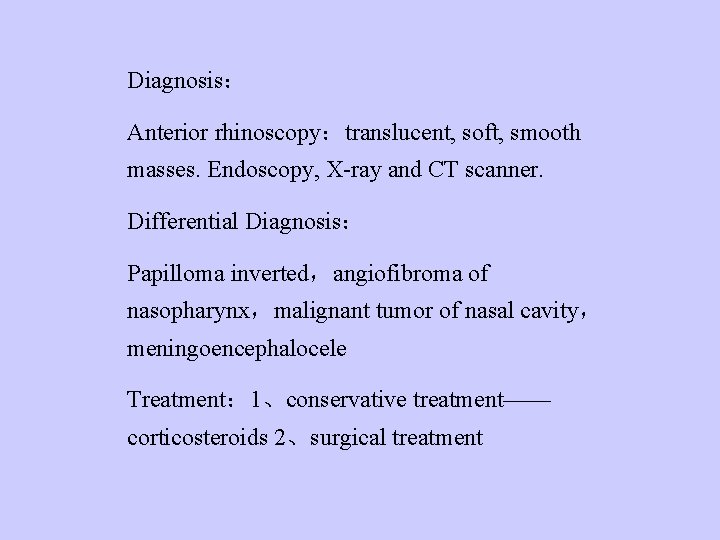

Diagnosis: Anterior rhinoscopy:translucent, soft, smooth masses. Endoscopy, X-ray and CT scanner. Differential Diagnosis: Papilloma inverted,angiofibroma of nasopharynx,malignant tumor of nasal cavity, meningoencephalocele Treatment: 1、conservative treatment—— corticosteroids 2、surgical treatment